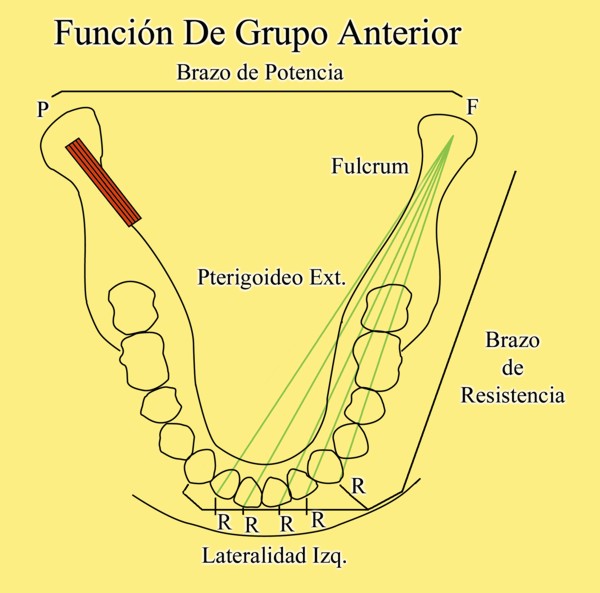

La primera de ellas: EL MOMENTO DE LOS BRAZOS DE POTENCIA EN LAS PALANCAS GENERADAS.

En un esquema de lateralidades a la izquierda, observamos que el Fulcrum de la misma lo encontramos en el cóndilo izquierdo, Cóndilo de Trabajo, la Potencia se encuentra en la fuerza generada por el Pterigoidéo Ext. del lado derecho, Cóndilo de No Trabajo, y la resistencia se dispone, en el caso de una FUNCIÓN DE GRUPO, en las Crestas Triangulares Internas de la tabla premolar-molar superior, que rozan contra las Crestas Centrales antagonistas ,correspondientes al inferior.

Por lo tanto, el Brazo de Potencia se establece entre el CnT(POTENCIA),y el CT(Fulcrum), mientras que los Brazos de Resistencia de las distintas piezas que intervienen en la Función de Grupo, se encuentran entre estas piezas y el CT(Fulcrum).

Como podemos ver en el esquema, estos son menores que el Brazo de Potencia y por lo tanto la fuerza generada por el mismo, producirá mayor deterioro , pues la palanca no está equilibrada:

EL BRAZO DE POTENCIA ES MAYOR QUE EL DE RESISTENCIA (Fig.6)

En el, todos o algunos de los dientes anteriores colaboran con la FUNCIÓN CANINA, siendo un mecanismo de elección en la reconstrucción del S.E., cuando carecemos de canino o cuando este es implantado.